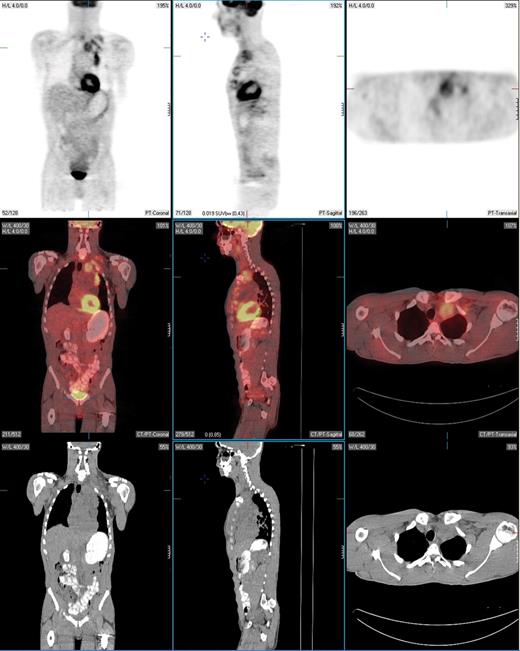

PET-positive residual mass in the anterior mediastinum extending into the left supraclavicular region in a patient with nodular sclerosis Hodgkin lymphoma. This patient underwent a restaging PET/CT scan 2 months following treatment with 6 cycles of ABVD. Fused PET/CT images show that the residual mass uptake is clearly greater than that of mediastinal blood pool structures, consistent with persistent disease. This was confirmed by fine needle aspiration and the patient then underwent salvage chemotherapy.